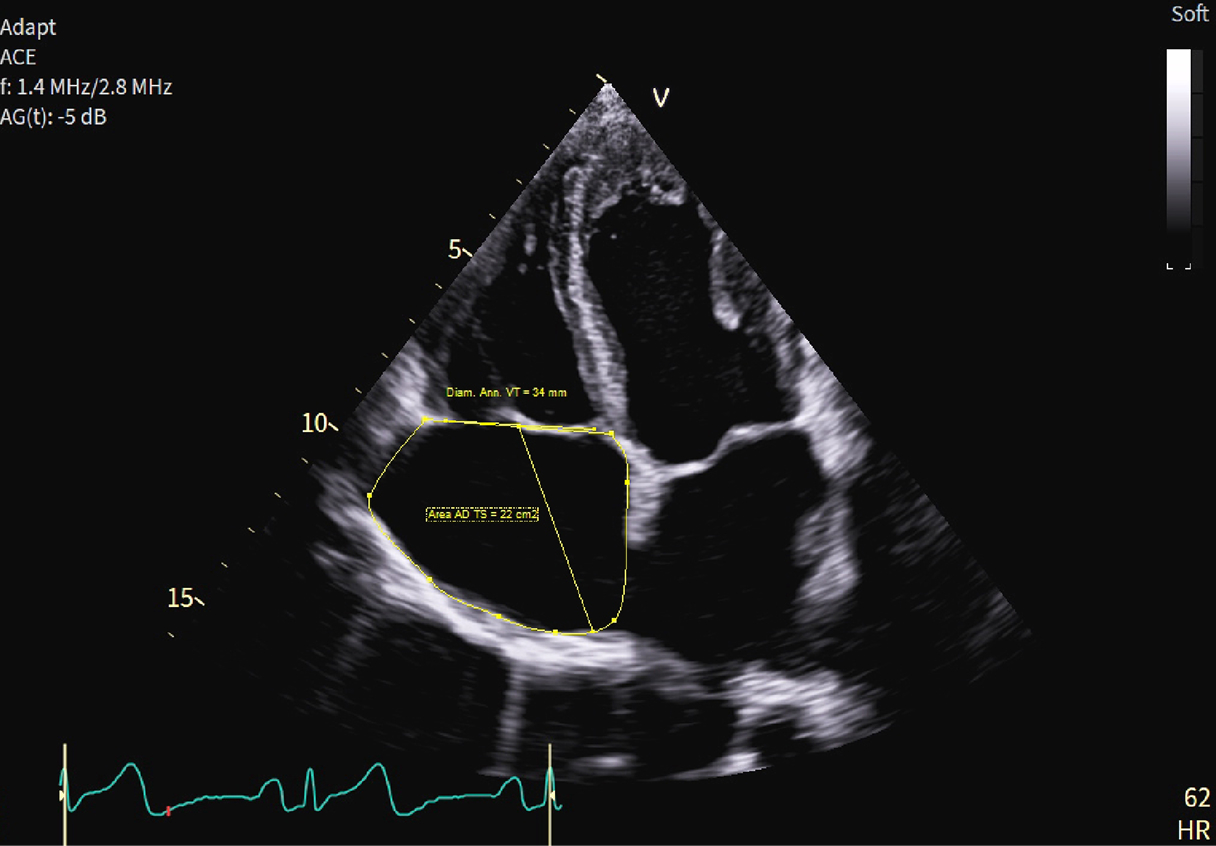

Caso condiviso da Marcello De Santis